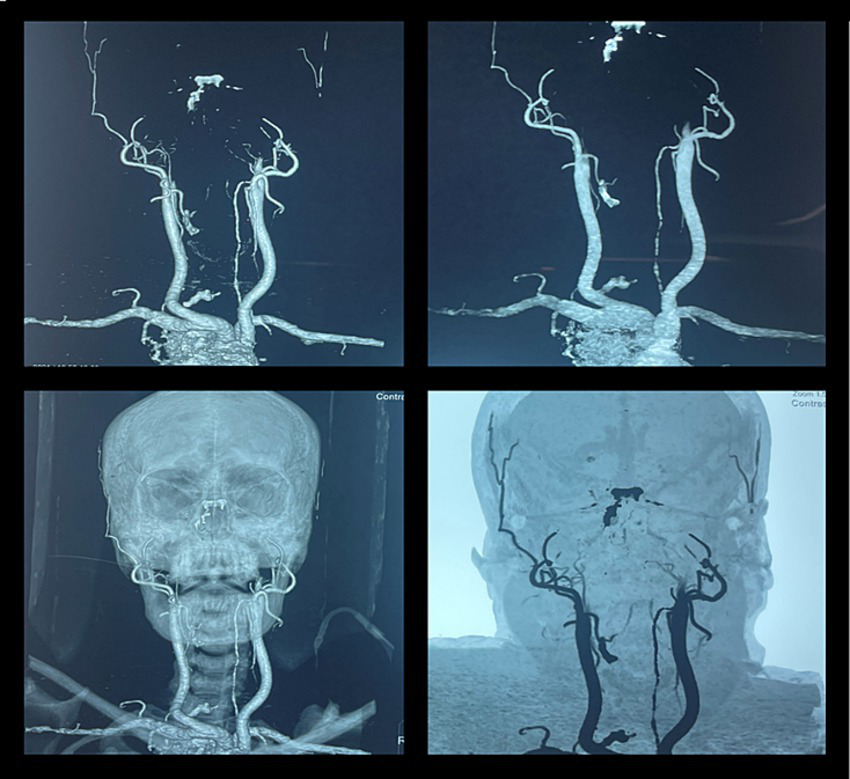

CT angiography and MR angiography

Several studies have also demonstrated the use of CTA for the diagnosis of brain death (31, 32). The majority of these can be applied to individuals who are heavily sedated, and their utility is predictive rather than confirming (32). When a patient has clinical ambiguity about their diagnosis, CTA can provide some evidence to support the diagnosis of brain death by indirectly demonstrating the absence of contrast opacification of cerebral arteries (Figure 6) (32). While the specificity of CTA for diagnosing brain death is described as 100%, sensitivity ranges from 52 to 97% (33, 34).

Figure 6

CT angiography in brain death. A 46-year-old woman was brought to our emergency department after a fatal motor vehicle accident. Her Glasgow Coma Scale (GCS) score was three on arrival. She had bradycardia and hypotension. The CT scan of the head showed a massive subdural hematoma with mass effect and compression of the brainstem with signs of herniation. She was intubated to secure the airway, and ICP was monitored by a subdural electrode. The raised ICP remained refractory to standard medical therapy, and her neurologic status progressively deteriorated and remained unresponsive. She further developed fixed dilated pupils, and her clinical findings were suggestive of brain death. The CT angiography showed non-opacification of the intracranial arteries beyond the internal carotid artery, suggestive of brain death.

MRA has been reported to carry a high sensitivity (93–100%) and specificity (100%), probably related to the additional, reliable, and detailed information about cerebral parenchymal changes (35, 36). MRA is rarely performed for the diagnosis of brain death as it is time-consuming, especially in critically ill patients. Furthermore, the commonly used “time-of-flight” sequences are not reliable due to their poor sensitivity to slow flow.

While interpreting the results of CTA, DSA, or MRA, clinicians should be cautious of the false-positive results in patients with hypotension and false-negative results in patients who have undergone decompressive craniectomy (22).